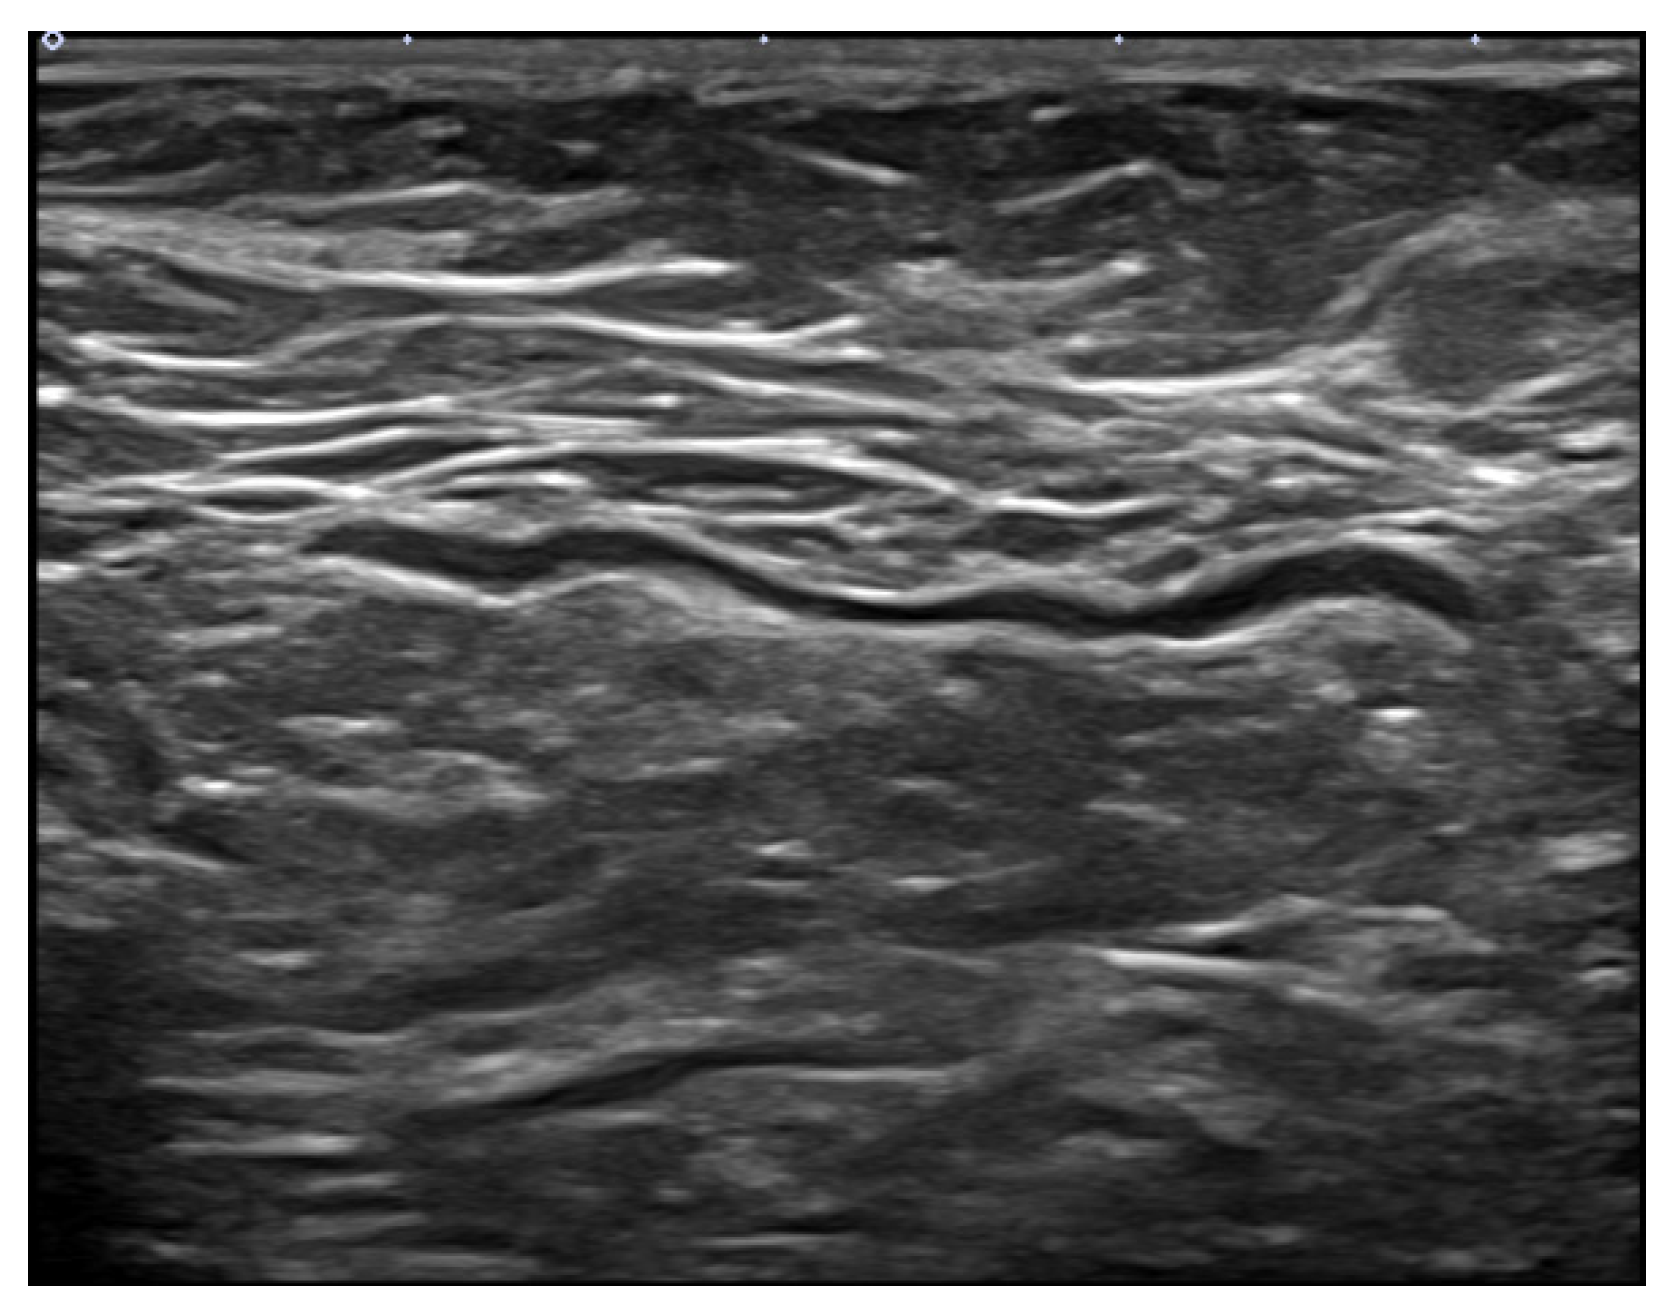

- Cocco, G.; Delli Pizzi, A.; Fabiani, S.; Cocco, N.; Boccatonda, A.; Frisone, A.; Scarano, S.; Shiavone, C. Lymphadenopathy after the anti-COVID-19 Vaccine: Multiparametric ultrasound findings. Biology 2021, 10, 652. [Google Scholar] [CrossRef]

- Granata, V.; Fusco, R.; Setola, S.V.; Galdiero, R.; Picone, C.; Izzo, F.; D’Aniello, R.; Miele, V.; Grassi, R.; Grassi, R.; et al. Lymphadenopathy after BNT162b2 Covid-19 vaccine: Preliminary ultrasound findings. Biology 2021, 10, 214. [Google Scholar] [CrossRef]